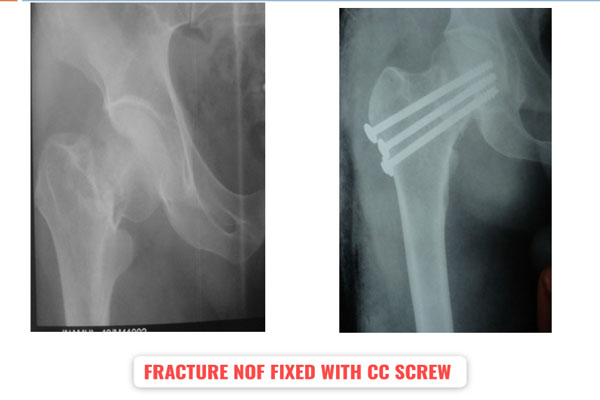

Fracture of bones is commonly handled by almost all orthopaedic surgeons in India. But dealing with comminuted intra-articular fractures (involving joints) is a night mare for most of them. It requires special expertise and experience to deal with such kind fractures. It can involve pelvic acetabular fracture, upper portion of thigh bone ( hip), lower portion of thigh bone ( femur), upper portion of arm bone (humerus head), lower portion of arm bone (humerus), lower portion of forarm bone (lower end of radius) fracture of heel bone, etc. The idea is to maintain the joint (articular) integrity and prevent the permanent loss of movements at that joint. It requires image intensifier (c-arm) to do these surgeries. May be artificial bone or autograft (patient’s own bone taken from iliac bone) to fill in the bone defect/ loss if present. The fracture may take 2- 3 months to heal. Patient may require prolonged physiotherapy to gain near normal range of motion exercises.